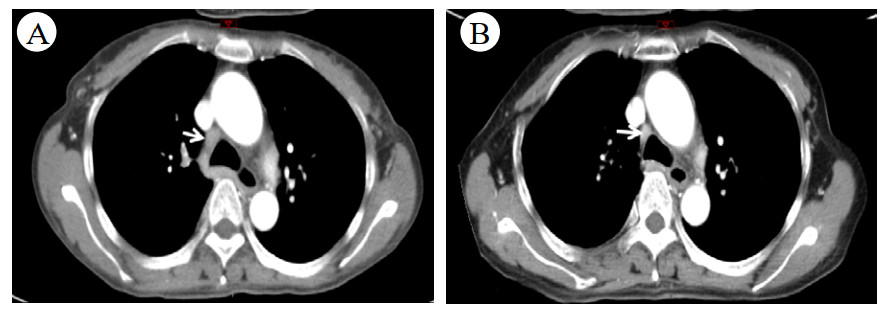

患者于2019-06-17因发热及头痛等不适来本院诊治。查体:体温38.5℃, 心率96次/min,呼吸20次/min,血压132/92 mmHg(1 mmHg=0.133 kPa)。结合症状及既往就诊经历,诊断考虑:发热查因;肺门淋巴结肿大。鉴别诊断:肺结核、淋巴瘤、结节病。同时患者外周血白细胞(WBC)及降钙素原(PCT)升高,不排除细菌感染, 予莫西沙星400 mg治疗5 d, 并在应用抗生素前留取病原学标本。期间行经气管镜超声引导针吸活检术(endobronchial ultrasound-guided transbronchial needlle aspiration, EBUS-TBNA),但无阳性结果。入院后所行的PET-CT提示肿大淋巴结考虑淋巴瘤。双肺小结节,考虑炎性肉芽肿。骨穿无异常结果, 以“肉芽肿(纵膈淋巴结)”为主要诊断出院。图 1为入院后两次胸部平片影像检查结果,可见右肺门影增浓。

| A:2019-07-15检查;B:2019-08-27检查 图 1 CT检查示右肺门影改变 |

后再因“反复发热、多关节痛7月、皮疹3月”于2019-09-17入住本院风湿科。入院当天体温36.5℃,心率106次/min,呼吸20次/min,血压118/75 mmHg。步态正常,自主体位。左颈部肿大淋巴结。四肢和背部可见紫癜样皮疹,按压部分褪色,伴抓痕。腹软,肝脾未及。图 2为2019-09-21胸部CT结果,箭头所指为肿大淋巴结。

| 图 2 胸部CT示纵膈淋巴结改变 |